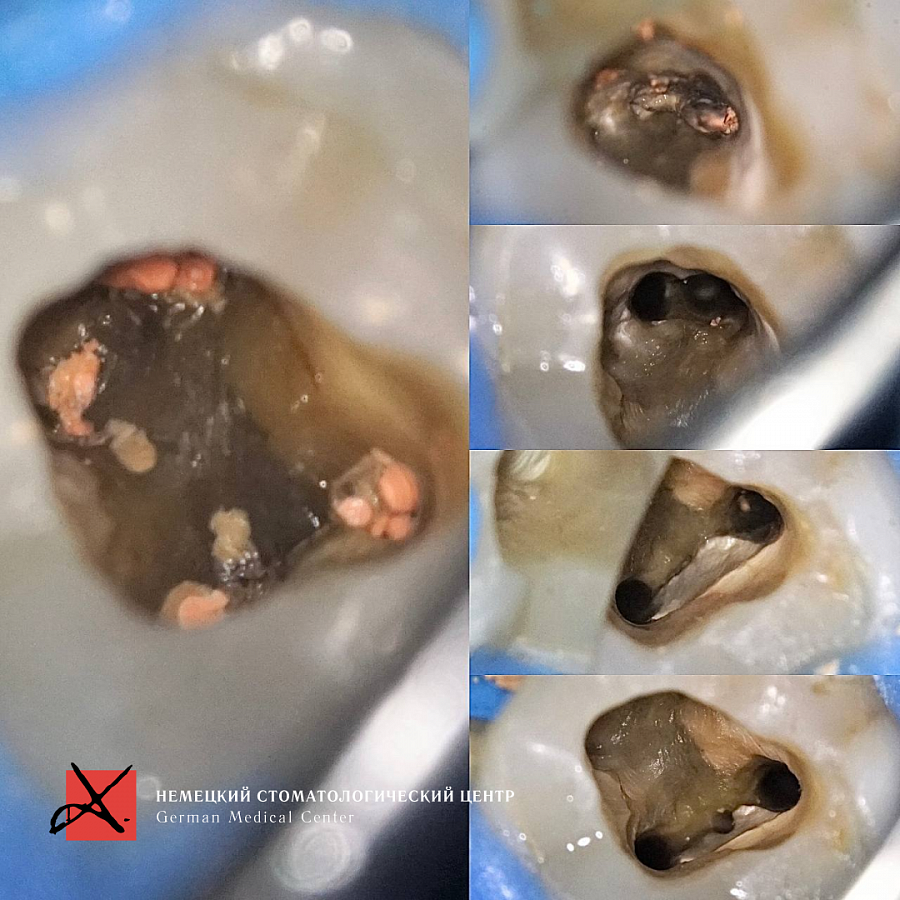

Этапы лечения

Лечение каналов под микроскопом

Результат лечения